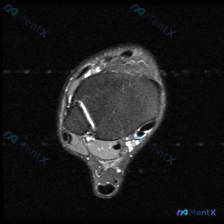

看到这张踝关节MRI,问题问有什么异常,很多人第一反应就是看到软组织积液,但其实背后藏着更关键的问题,我整理一下完整的分析思路给大家。 病例影像基础信息 这是一张踝关节MRI T2序列轴位影像,我们先把所有能看到的征象理清楚: 1. 骨骼结构:影像中心是距骨横截面,皮质骨低信号、骨髓中等信号,骨质轮...